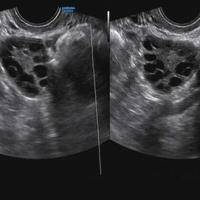

试管促排期间做b超检测看到的卵泡数量准确吗?

问题描述:我目前正在做试管促排卵治疗,在这期间医生叮嘱我要多次到医院去做卵泡发育监测。昨天我刚去做了检测,说是有10个左右卵泡发育较好,但我觉得B超检查结果也会有一定差异,因此想问问这期间检查看到的卵泡数量准确吗?最佳回答:不一定。在试管促排期间,会因为B超观察角度、卵泡发育动态和医生经验存在观察到的卵泡数量差异。在试管促排卵期间,通过B超检测能帮助医生评估卵巢内卵泡的数量、大小和发育情况,这些信...